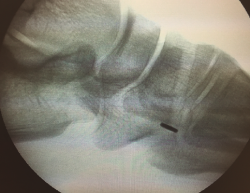

A continuación, se procede a localizar la inserción del TA sobre la cuña medial, diseccionando la región escafocuneana y verificando el punto de inserción mediante escopia.

Una vez finalizado este paso, se asegura la estabilidad del sistema mediante la flexoextensión del tobillo (Figura 8) y se comprueba con fotoescopia la correcta colocación de la placa metálica al nivel de la cortical plantar de la cuña medial (Figura 9).

Figura 9. Imagen de fotoescopia para comprobar el correcto posicionamiento de la placa metálica en la superficie plantar de la cuña medial.